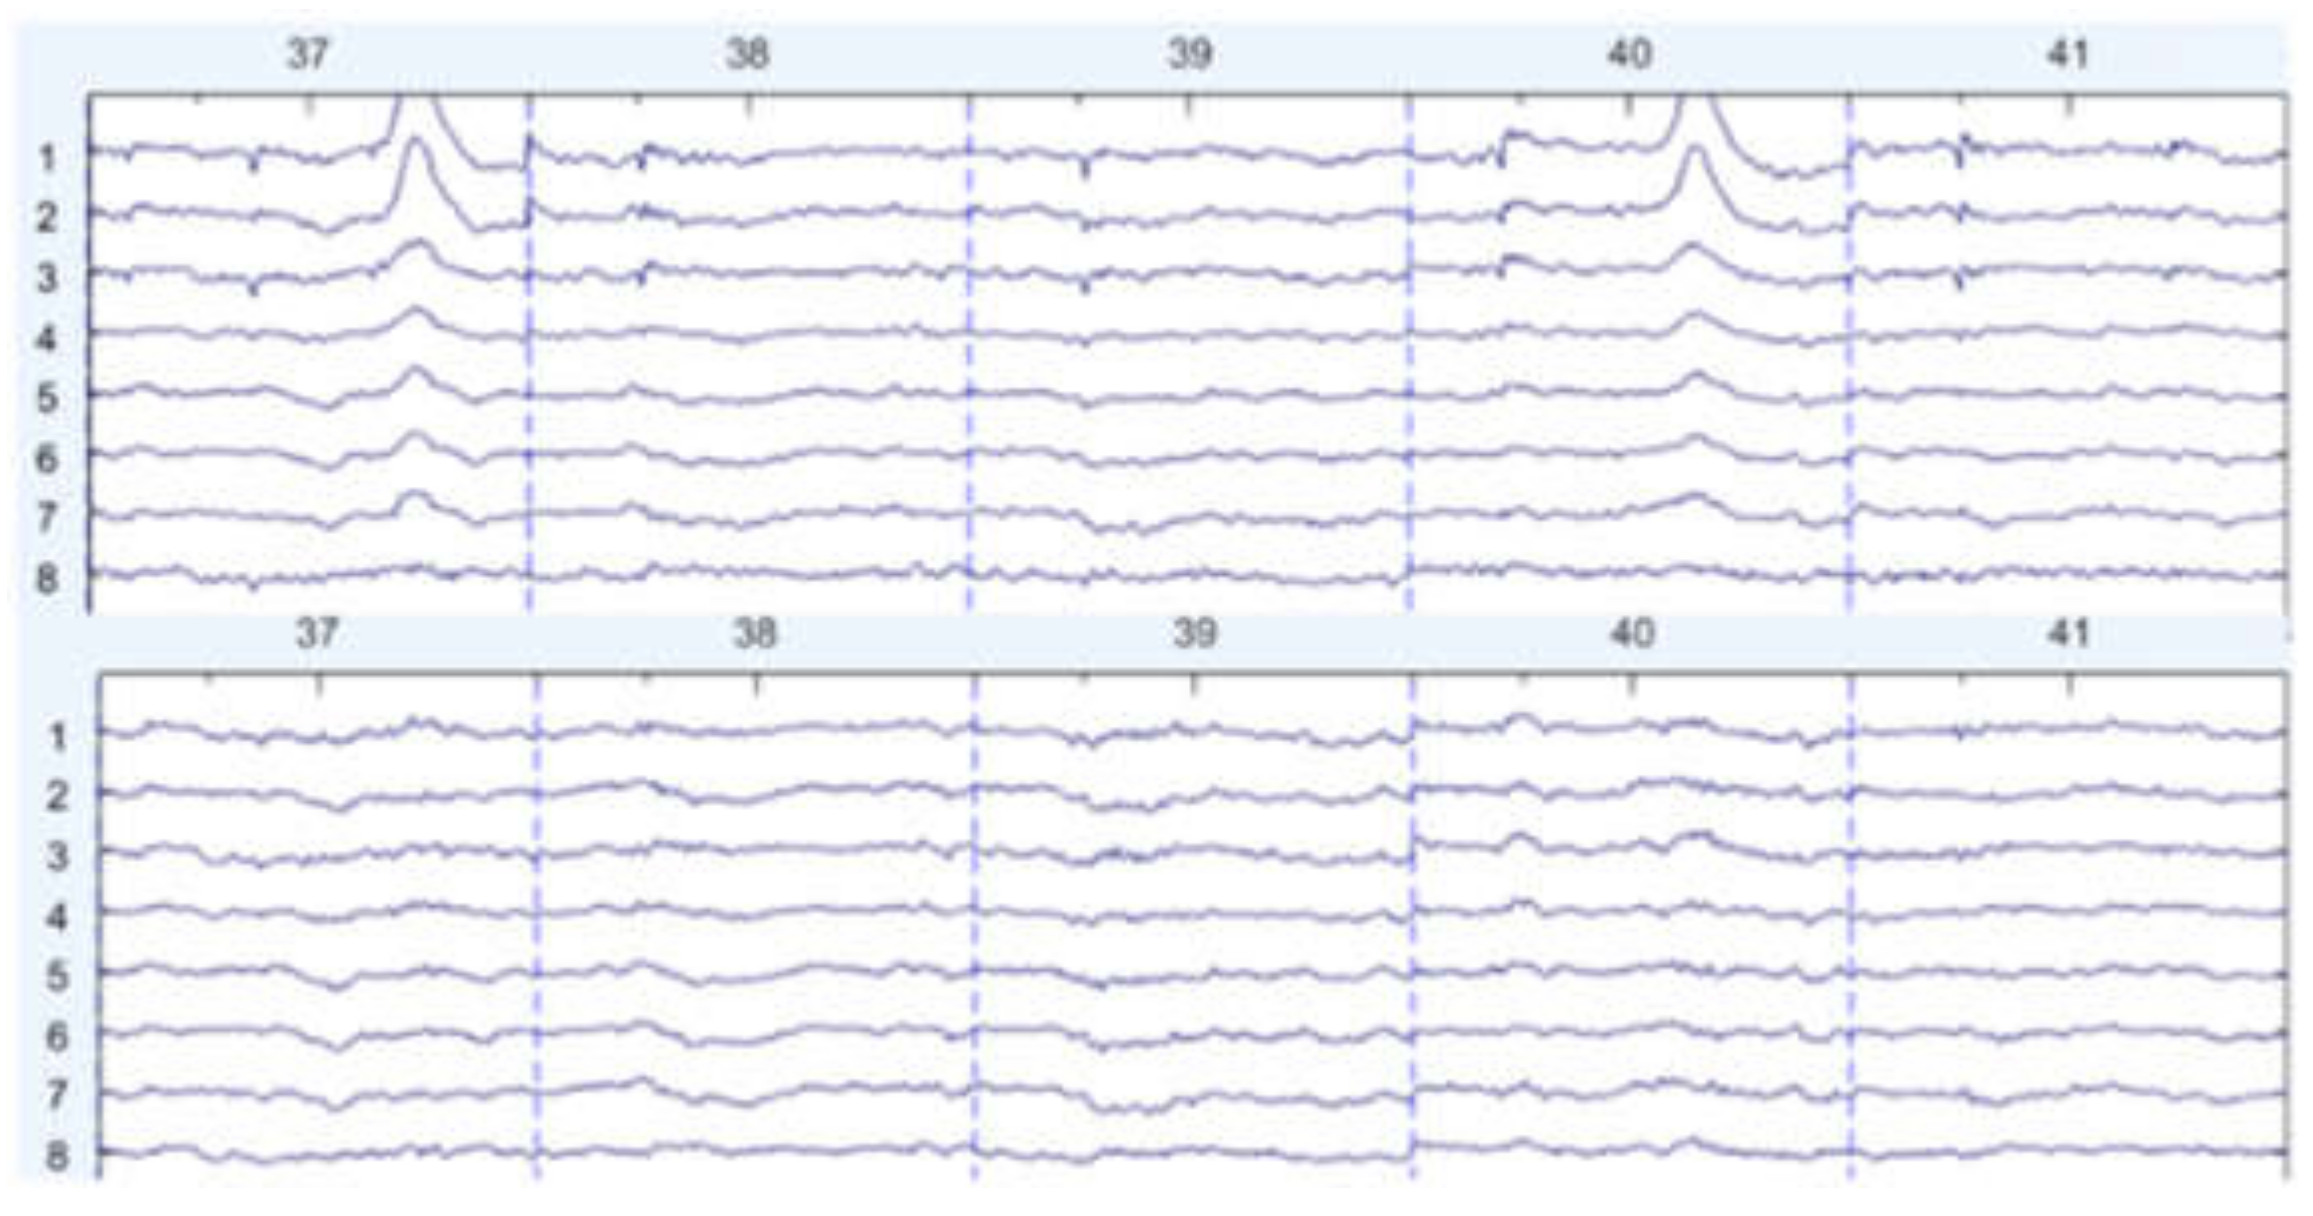

There are some graph results, which are shown in Figure 7, Figure 8 and Figure 9. They can be divided into three groups: the EEG data that are slightly affected, the EEG data that are moderately affected, and the EEG data that are seriously affected by noise signals. The top side of the figure is the original EEG signal while the bottom is the result after filtering.

Figure 7. Slightly affected by noise (noisy data at the top, filtered data at the bottom).

Figure 8. Moderately affected by noise (noisy data at the top, filtered data at the bottom).

Figure 9. Seriously affected by noise (noisy data at the top, filtered data at the bottom).